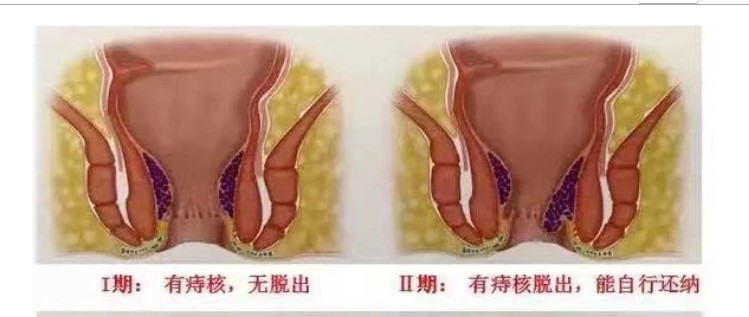

A:痔瘡是比較常見的肛周疾病,其發生的原因是由於直腸下端,或肛管周圍的黏膜曲張靜脈造成,屬於血管內病變。根據解剖部位的不同,齒狀線以上稱之為內痔,在齒狀線以下稱之為外痔。外痔可以使用稀釋的高錳酸鉀溶液進行坐浴,在坐浴以後同時配合麝香痔瘡膏、痔瘡……

A:痔瘡分為內痔、外痔、混合痔,外痔就是生長在齒狀線以下的一種腫物。這種疾病一般是由炎症以及靜脈迴流等原因所導致的,當病人患上外痔以後一般是可以看得見的,並且這種痔瘡不容易出血。如果病人讓腫塊受到摩擦的話,可能會病人出現疼痛等症狀。臨床上如果……

A:痔瘡是常見的肛周疾病,它是由直腸下段或肛管周圍的黏膜曲張靜脈造成。根據解剖位置的不同,齒狀線以上稱之為內痔,齒狀線以下稱之為外痔。外痔在臨床上大致可分為血栓性外痔、血管源性外痔、炎性外痔,以及結締組織性外痔。血栓性外痔大多是在外痔的血管團……